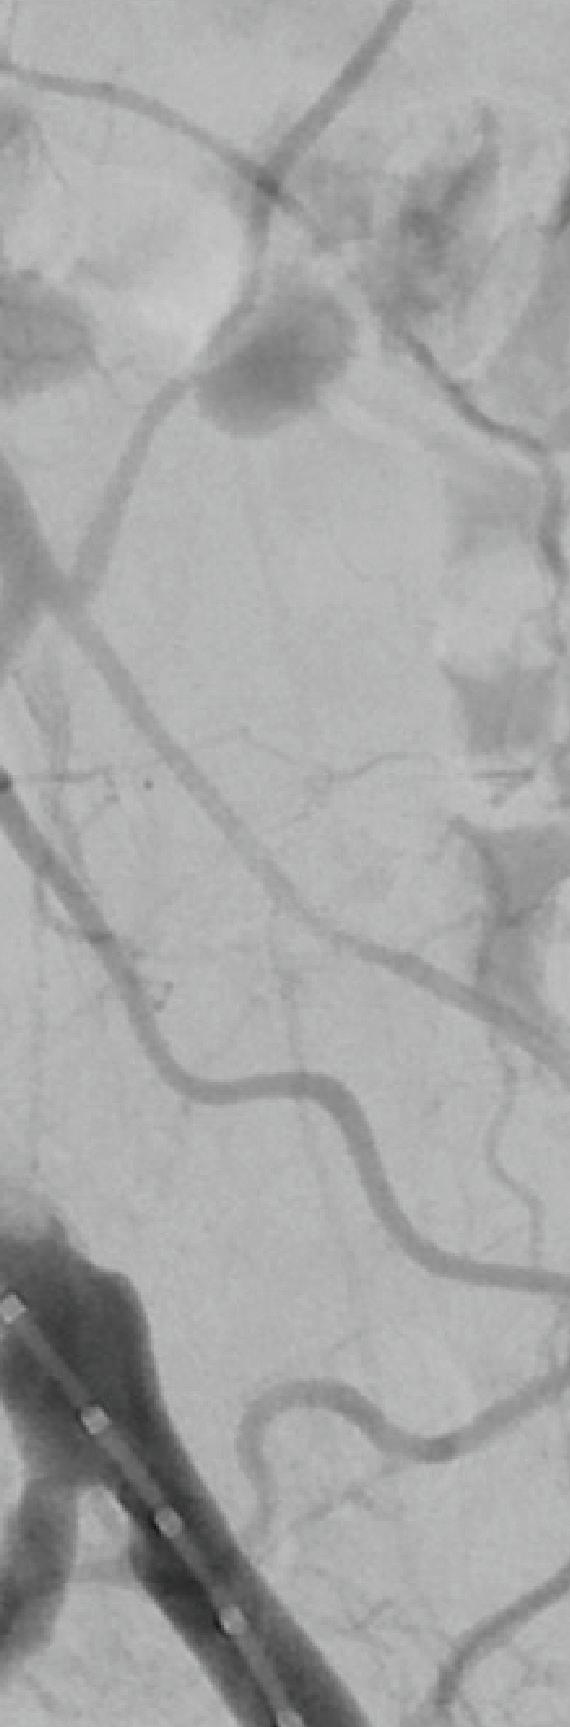

Initial IVUS confirmed the IST (A). Preprocedure venogram demonstrated instent thrombosis and impaired flow (B). Extracted thrombotic material (C). Postprocedure IVUS confirms stent patency (D). Postprocedural venogram confirms patency (E). RevCore Thrombectomy Catheter with expandable coring element (F)

Case report: Complete thrombus extraction after severe right EIV stent stenosis

A man in his mid-50s presented with ulceration and swelling in his right foot with the intention to transfer care. Several months prior, a right external iliac vein (EIV) to right common femoral vein (CFV) stent had been placed. A venous duplex ultrasound study showed proximal stent occlusion and non-occlusive venous thrombosis in the left proximal femoral, popliteal, posterior tibial, and gastrocnemius vessels, as well as thrombosed varicosities. Right lower extremity venography and intravascular ultrasound (IVUS) performed two-and-a-half weeks later confirmed 65% stenosis of the left EIV stent (image A). An in-hospital mechanical thrombectomy and balloon angioplasty procedure was planned.

Procedural overview

The patient was positioned supine and ultrasound guidance was used to access the right CFV. A J-wire was advanced into the IVC. An 8F sheath was placed and a venogram showed stenosis within the right EIV stent (B). Similarly, access was gained to the left CFV, and a J-wire was advanced into the IVC. An 11F sheath was placed and a venogram confirmed there was no stenosis in the selected segments.

A final IVUS showed nearly 100% lumen gain, restoring the right EIV to CFV in-stent diameter to 16.4 mm (D). A final venogram demonstrated appropriate flow through the right CFV, EIV, CIV and IVC, and resolution of the stenosis within the right EIV (E). The FlowTriever disks and all other devices were removed, and manual pressure was held.

Total procedure time: 40 minutes. Estimated blood loss: <50mL. The patient tolerated the procedure well. He was discharged on dabigatran the following day. At four-week follow-up, stent patency was maintained per venous duplex ultrasound, and the patient’s right lower extremity pain and edema had improved. Progress was also seen in a previously non-healing ulceration of the right foot.

Conclusion

Use of the novel RevCore system ( F) allowed for thorough extraction of in-stent thrombosis and complete lumen restoration post-thrombectomy, with sustained patency and symptom relief at follow-up. The results show promise for improving quality of life in patients who had exhausted their treatment options previously.